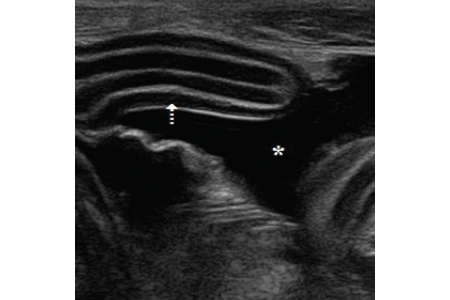

Laryngeal paralysis is the effect of an inability to abduct the arytenoid cartilages during inspiration, resulting in respiratory signs consistent with partial airway obstruction. The aetiology of...